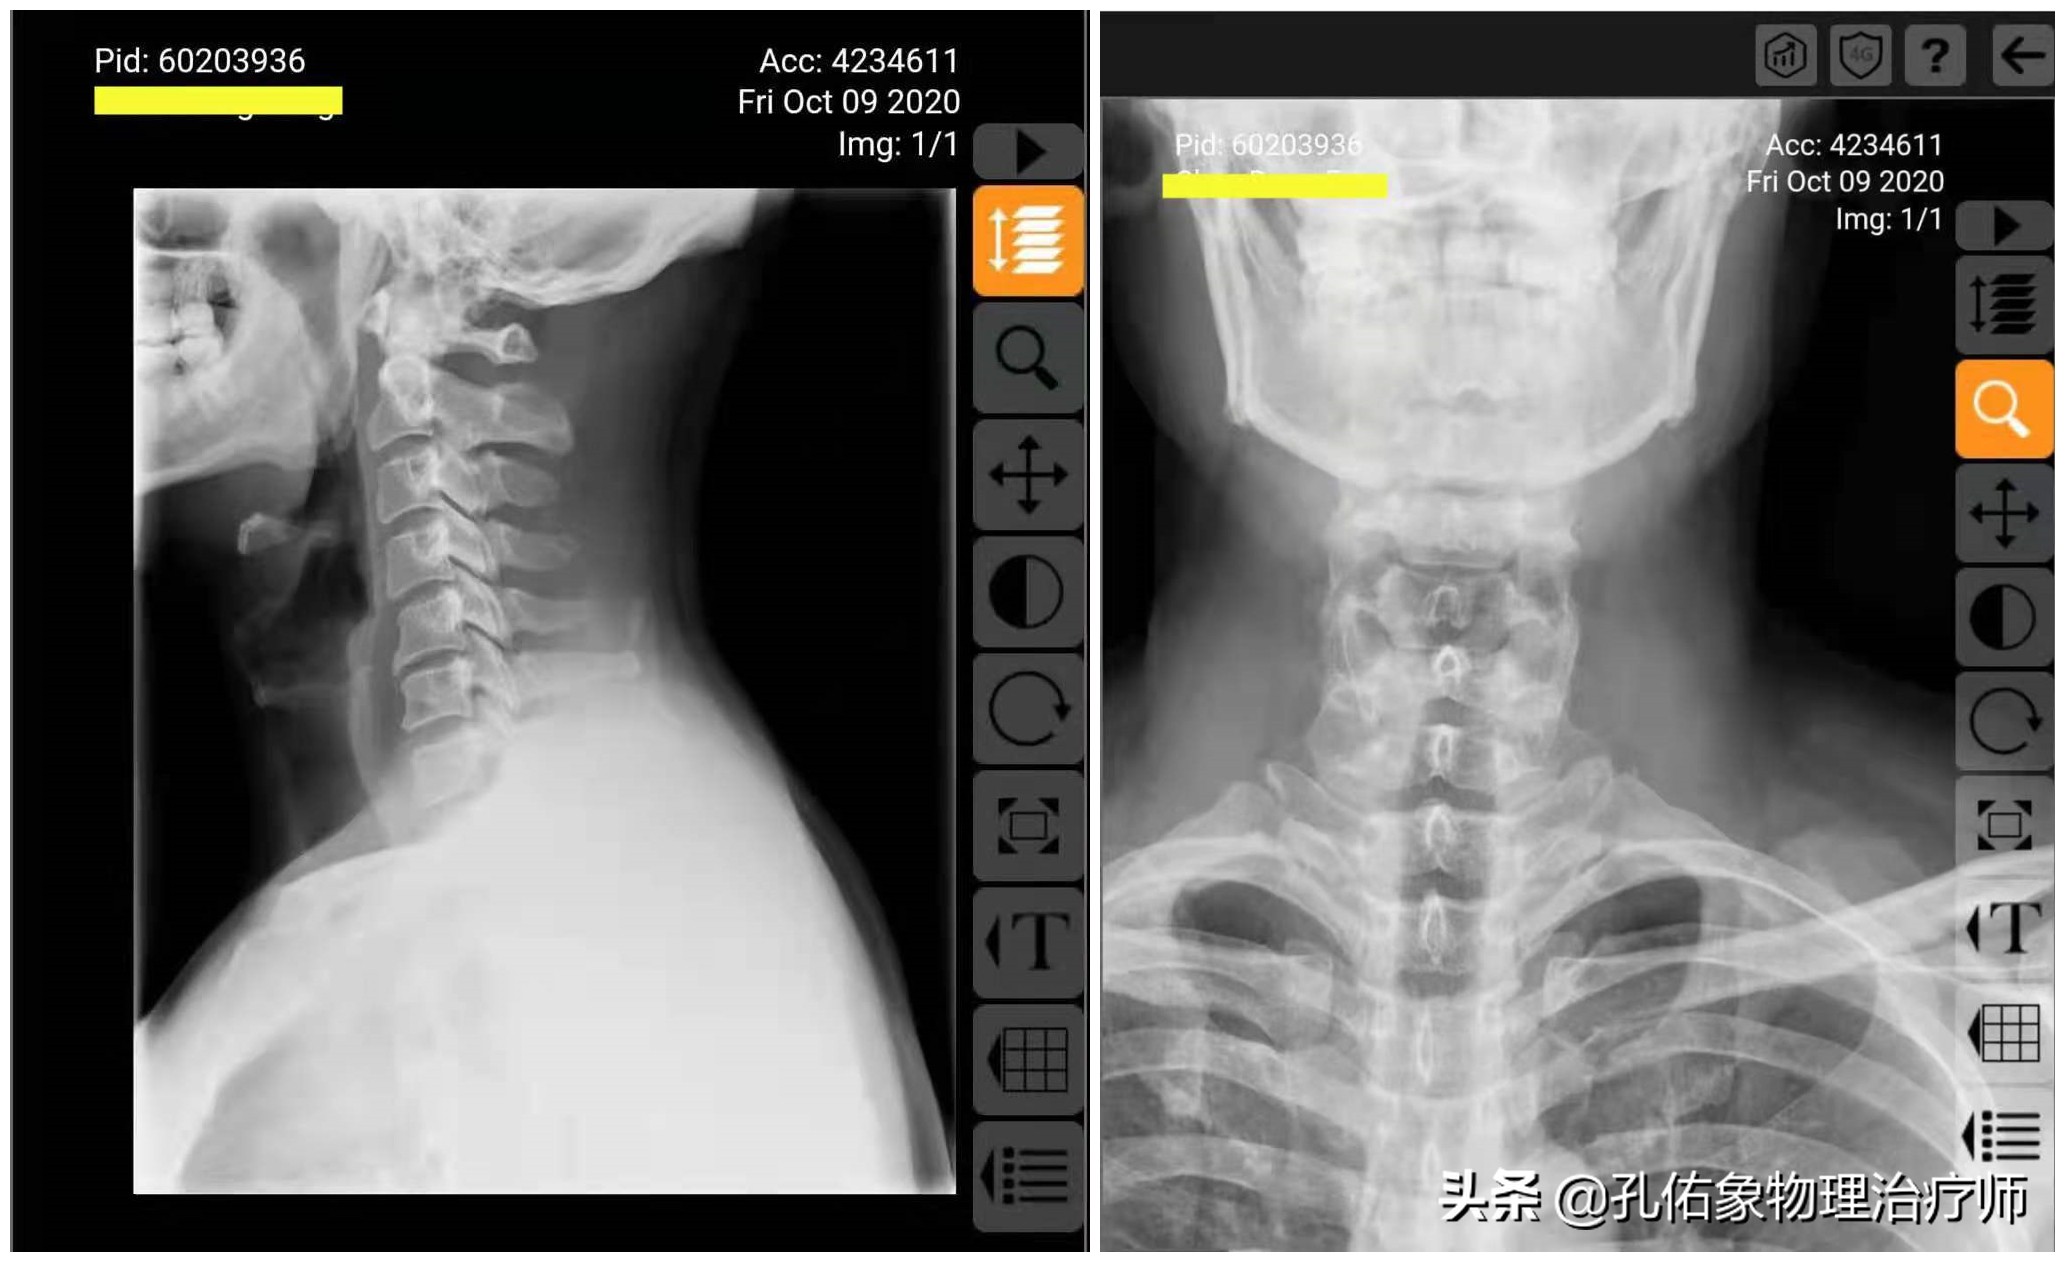

颈椎正、侧位片

上图所示的片子,是一位颈痛患者的正、侧位X片,影像科拍片大夫的报告单中是这样写的:

上文中的颈椎正侧位X片,在影像科大夫和非专业的人眼睛里,它反应的是颈椎问题,但对于治疗的人员,真没有治疗性的指导作用。

在专业治疗人员这,会重新分析解读颈椎的正侧位X片:

片子读完之后,可以详细得知该片子的患者主要颈椎问题是发生在第5颈椎,有骨质增生,椎体发生向后、向右、向下的错位,而第6、7颈椎发生向后、向左、向下的错位。这样就可以判断出颈6、颈7神经有卡压情形,结合相应神经支配区查体,两者是否吻合,再给予徒手治疗。